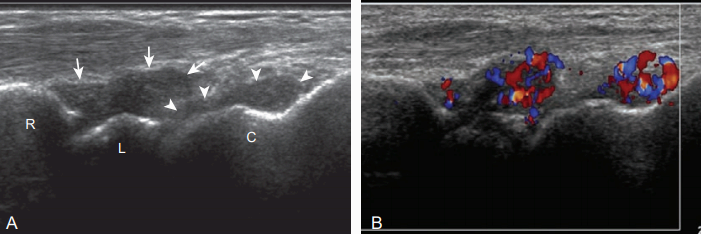

팽창된 관절오목내에 에코가 보이는 경우, 복합액과 윤활막염(synovitis)을 고려해야 한다. 두 원인 간의 구분은 어려울 수 있으며, 근육에 비해 낮은에코, 같은 에코, 또는 높은 에코 등 다양하게 보일 수 있다. 만약 관절오목 팽창이 탐촉자에 의한 압박으로 눌리거나 관절운동에 따라 내부에코가 움직이거나 또는 강화도플러영상(power doppler)에서 내부에 혈류가 보이지 않으면 복합액의 가능성이 높다. 반면에 관절오목이 거의 눌리지 않거나 색 및 강화 도플러 영상에서 혈류가 보이면 윤활막염의 가능성이 높다. 감별을 위하여 초음파유도하 흡인이 필요할 수 있다. 복합액과 윤활막염은 출혈, 판누스(pannus), 그리고 감염, 염증성관절염, 결정체(crystal) 침착에 의한 염증 등이 원인이다. 색소침착융모결절성 윤활막염(pigmented villonodular synovitis)과 윤활막뼈연골종증(synovial osteochondromatosis)등의 윤활막 증식성 질환도 원인이 될 수 있다. 이외에 윤활막 조직에 높은 에코 석회화가 생길 수도 있다.

손과 손목의 힘줄 이상에는 힘줄윤활막염, 힘줄증(tendinosis), 힘줄째짐이 있다. 힘줄윤활막염은 힘줄주의 윤활집(synovial sheath)의 팽창이 특징이며, 관절오목팽창과 마찬가지로 내부에 에코가 없는 경우 단순액을 시사한다. 만약 팽창된 힘줄집(tendon sheath) 내에 에코가 있으면 복합액과 윤활막염의 구분이 필요하다.

탐촉자로 눌렀을때 압축성과 내부 에코의 움직임, 그리고 색 및 강화도플러 영상에서 혈류가 보이지 않으면 윤활막염보다 복합액을 시사한다. 반면에 압박되지 않거나 색 도플러영상에서 혈류가 보이면 윤활막염을 시사한다. 힘줄윤활막염의 원인으로 퇴행성, 외상성, 증식성, 그리고 감염 또는 결정체 침착에 의한 염증성 질환 등이 있다. 노손목관절 부위에서 정상 폄지지띠를 힘줄윤활막염으로 오인하지 않는 것이 중요하다. 정상 높은 에코의 지지띠가 비등방성에 의해 낮은 에코로 보여 혼란을 일으킬 수 있다. 첫 번째 손목 구획 내의 짧은 엄지폄힘줄과 긴 엄지 벌림 힘줄에 생기는 협착성 힘줄윤활막염(stenosing tenosynovitis)을 드쿼베인 힘줄윤활막염(dequervain's thenosynovitis)이라고 한다. 이 질환은 힘줄 주위 조직의 비후, 혈류증가, 힘줄증, 그리고 노뼈의 불규칙한 뼈겉질 소견을 보이고 통증을 동반한다.